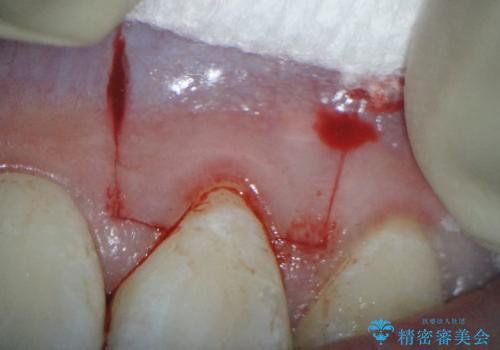

前歯の歯肉退縮 歯周形成外科(歯冠側移動術)

- 上顎左側側切歯の歯肉退縮を主訴に来院されました。

生活に支障はないが審美的要求が強く歯肉形成外科(歯冠側移動術)を行うこととしました。

根面被覆術には結合組織を用いる場合もありますが、今回のケースでは、角化歯肉が十分あり、審美性の要件が強いため、隣在歯との調和が取りやすい歯冠側移動術のみで対応しております。